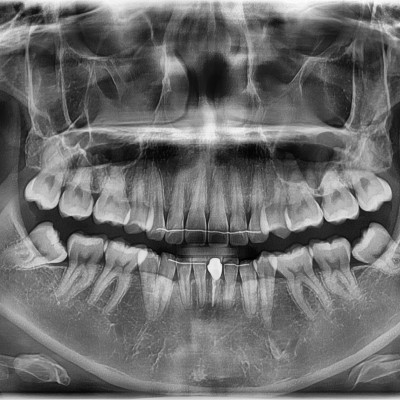

#18,28,38,48 사랑니 발치 #18,28,38,48 사랑니 발치 구강 외과 전문의가 당일 발치했습니다. --------------------..

작성자 이턱이 작성일 02-09 조회 43